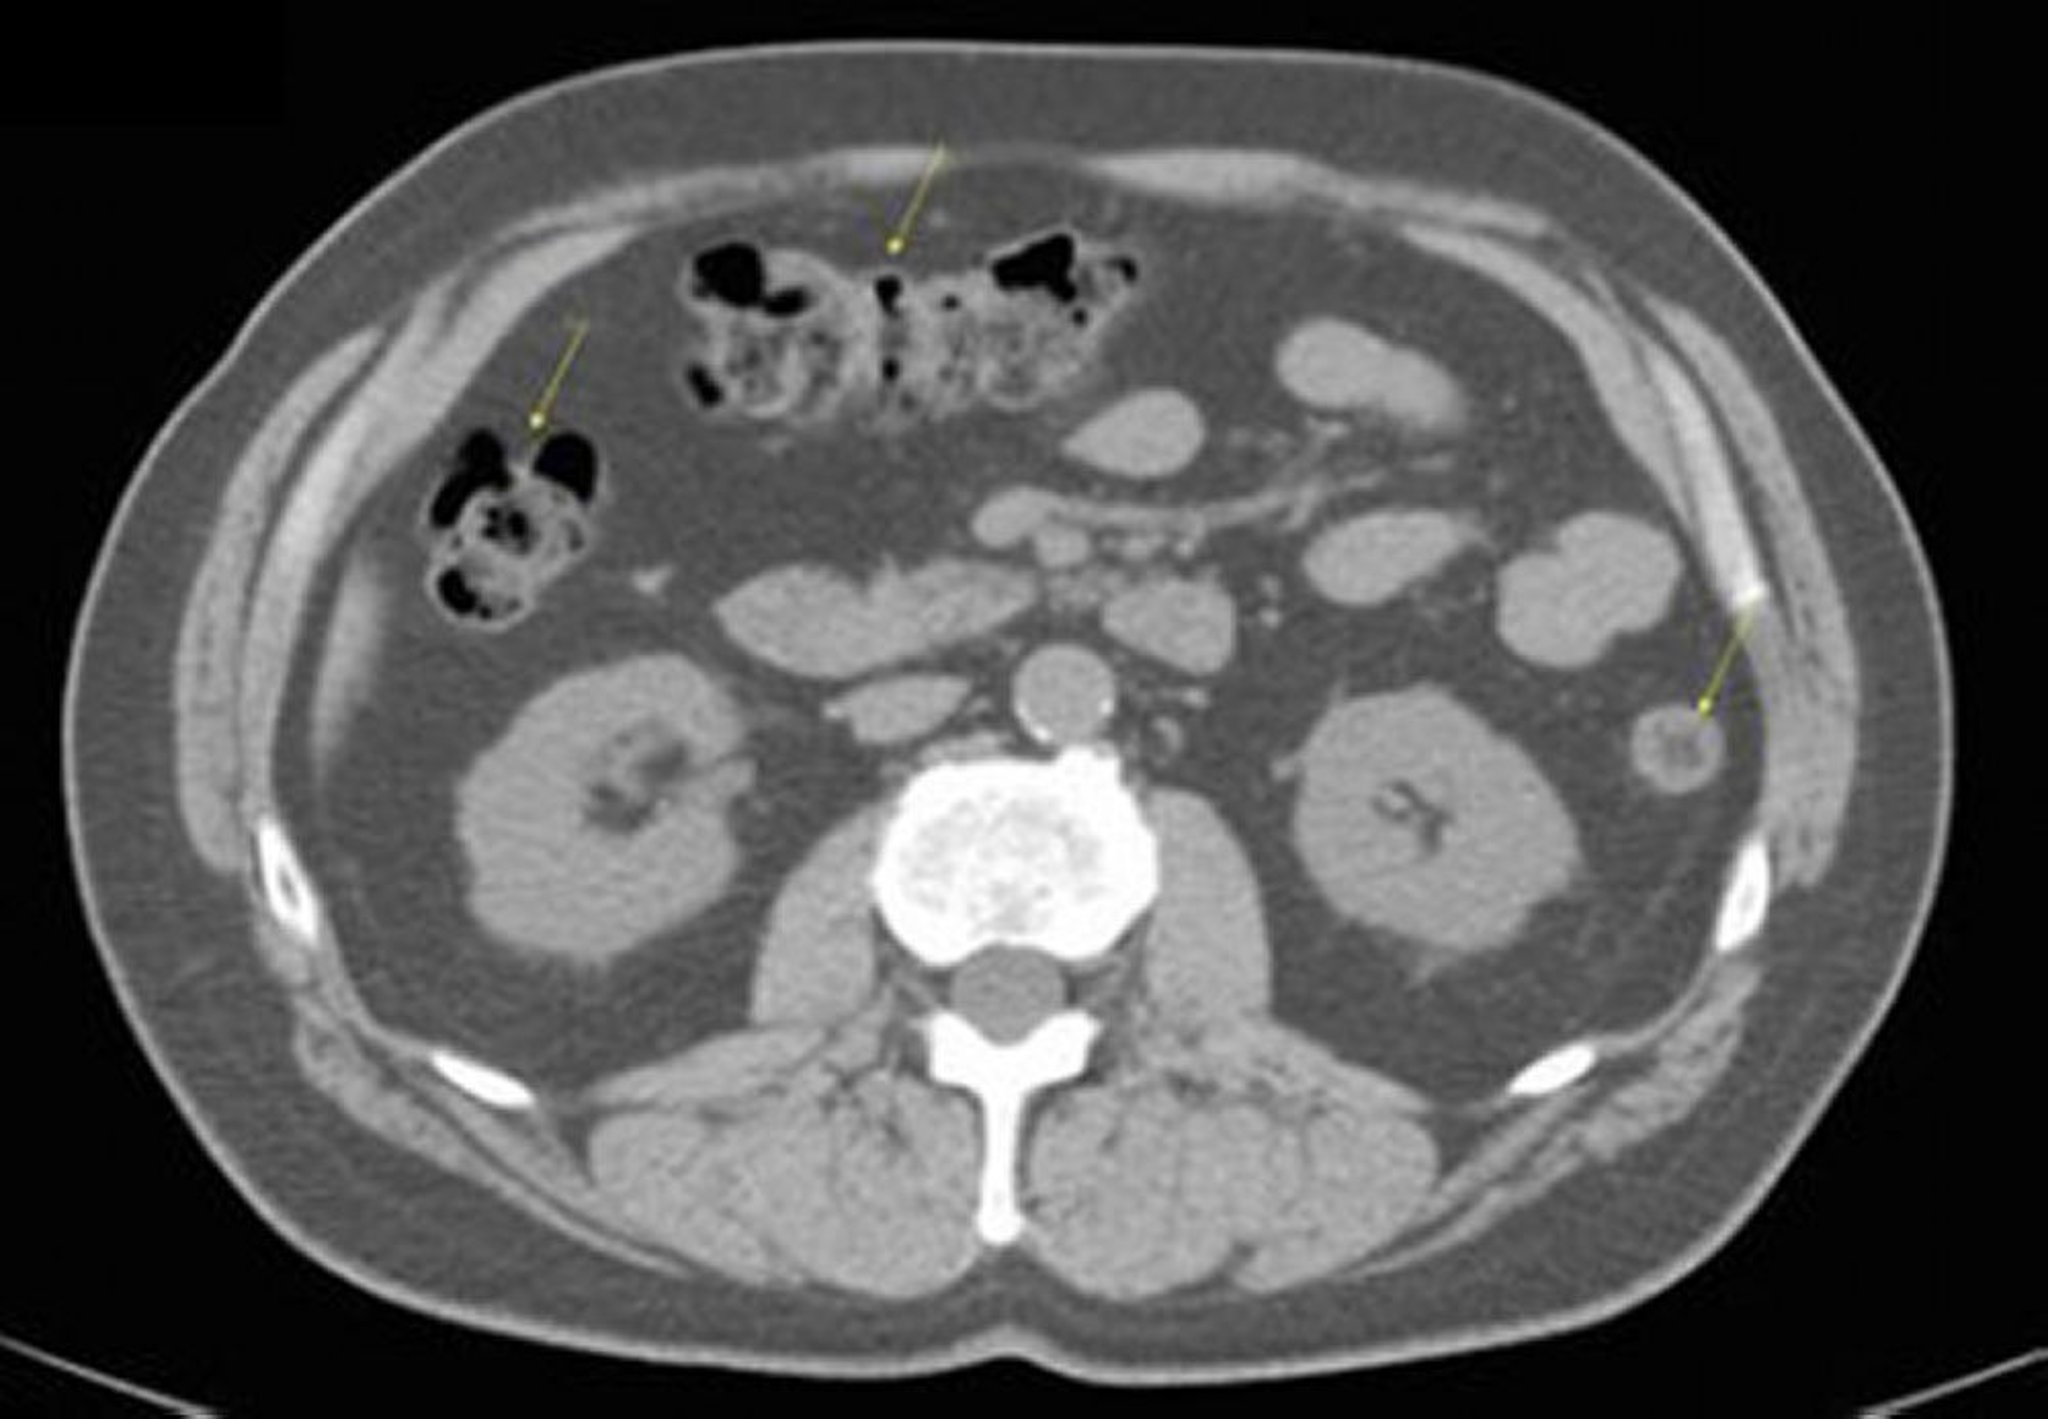

CT-Scan von Abdomen und Becken mit normaler Anatomie ohne Kontrastmittel (Folie 17)

Dieses Bild zeigt das Kolon (Pfeile).